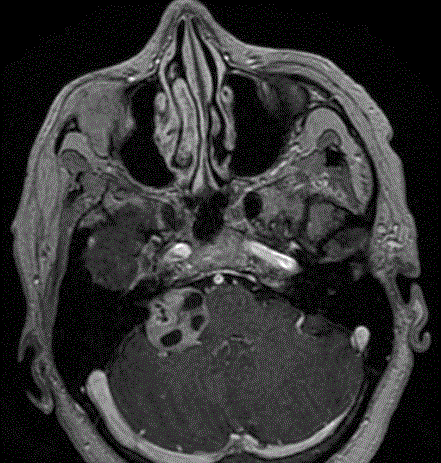

Les neurinomes de l’acoustique

Ce sont des tumeurs bénignes à croissance lente développées au dépens du nerf vestibulaire reliant l’oreille au cerveau. Aussi appelé schwannomes vestibulaires, ces tumeurs peuvent croître et endommager le tronc cérébral et les nerfs crâniens adjacents lors de leur développement. Les symptômes comprennent des troubles de l’équilibre ou des instabilités, une perte auditive et/ou des bourdonnements (acouphènes) dans l’oreille affectée.

Le traitement comprend la surveillance radiologique, la chirurgie ou la radiothérapie stéréotaxique. La chirurgie est réalisée par les membres de l’équipe du service ORL spécialisés dans cette chirurgie. Ensemble, ils décident de la meilleure façon d’aborder et enlever la tumeur tout en préservant la fonction nerveuse du visage. Un surveillance de la de la fonction du nerf faciale (monitoring) est effectuée pendant toute la durée de la chirurgie.

Une autre option de traitement réside dans la radiochirurgie stéréotaxique, un type de radiothérapie qui peut concentrer les rayons X à haute puissance sur la tumeur.

Différents stades du neurinome (d’après Jackler, ATLAS OF SKULL BASE SURGERY & NEUROTOLOGY. Thieme. ©2009)